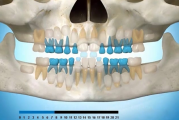

Vali sind huvitav pilt ja me näitame sellega seotud haigust ja sümptomeid